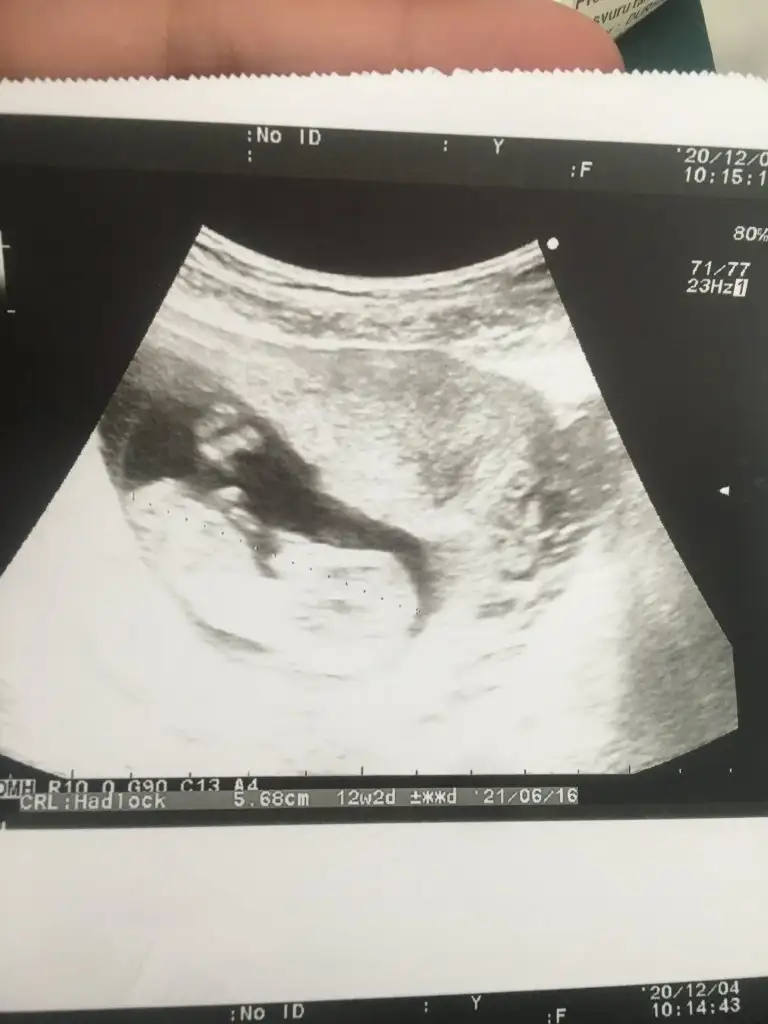

Kesenin şekli cinsiyeti belirlemiyorbende baktım dedim ne sag ne sol bu nedir acaba yuvarlak kese kız ihtimalimi yüksek oluyodu sanki öyle hatırlıyorum ama yinede atarım bidahaki kontrolde düşük riskim var malesef dua edin

Evet iyi olur emin olalim en azındanPazartesi 13 haftalık olacağım o zaman tekrar atayım başka doktora gideceğim onun tahminini de yazarım. İnşallah kızdırAslında ikiz hamileydim çift yumurta biri kız birisi erkek oluyorlar genellikle. Kesemin birinde plesanta oluştu bebek gelişmedi. Hangisi daha güçlüydü o yönden de merak var hala aynı boyda iki kesem var çok üzücü.

Kız bence ikiside ama ikra meyrada baksın yinedemerhaba anneler, benim bebelerim için de tahminde bulunurmusunuz. 6 haftalık vajinal ultrasyon

Ya benim içime nedense erkek doğdu kemik yapısını oğlumun usg sine benzettim:)))Bebeğin düz durduğu videodan ben çektim umarım doğru pozisyonu yakalamışımdır. Doktor bir tahminde bulunmadı 13+0 merak ediyorum artık